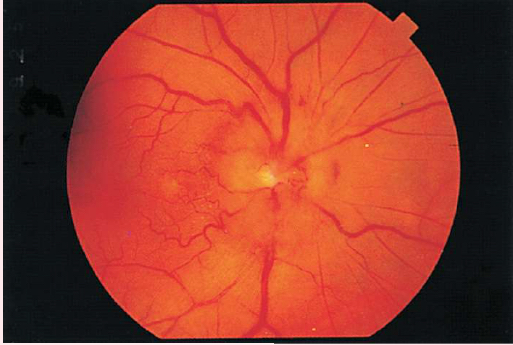

PAPILLEDEMA

Swollen optic disc

Blurred margins

Hyperemic appearance from accumulation of excess blood

Visible and numerous disc vessels

Lack of visible physiologic cup